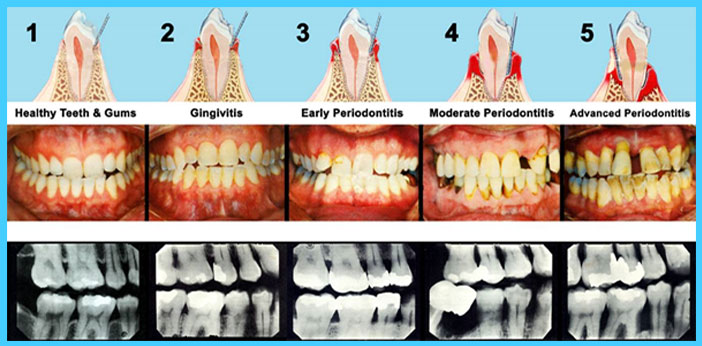

Periodontal disease is an inflammation of the gums caused by bacteria. The bacteria cause plaque to develop along the gum line. The infection will cause the gums to swell and bleed. In addition, the plaque will cause damage to the bone that supports teeth. For most people, flossing and brushing at least two times each day along with professional cleanings will help prevent gingivitis and Periodontal Disease.

Bacteria that cause plaque produce toxins that cause inflammation of the gums. The gums will appear red and swollen. Many people will notice bleeding while brushing their teeth. This is an indication professional treatment is required.